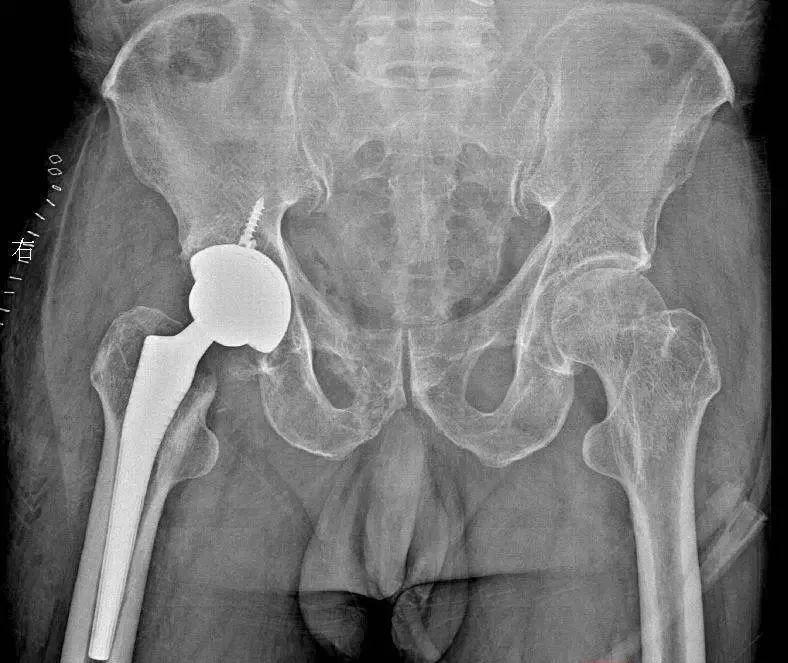

成功接受右侧髋关节置换手术

针对潘先生的病情,镇江市中西医结合医院骨科团队制定了精准的髋关节置换方案。手术采用微创关节置换 DAA入路,最大限度减少创伤。术后第二天,潘先生便在康复师指导下开始行走训练。